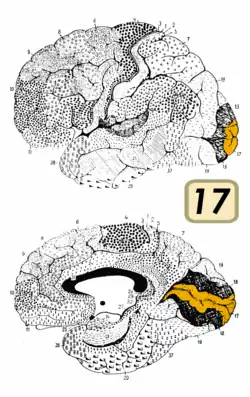

El lóbulo occipital muestra una forma piramidal con vértice posterior en el polo occipital. Su cara lateral externa es convexa, su cara interna o medial es plana y su cara inferior es ligeramente cóncava.

La cisura calcarina, situada en la cara medial, atraviesa la superficie interna del lóbulo por su parte media, extendiéndose desde la extremidad posterior del polo occipital, hasta la cisura parieto-occipital.[7]

El área visual lleva el nombre de "corteza estriada", porque deriva de la estría de Gennari, una banda distintiva visible a simple vista y el único marcador anatómico que indica el área visual primaria.

La corteza visual, está conformada por el área estriada, llamada visual primaria (V1) y por las áreas visuales corticales extra-estriadas, nombradas como V2, V3, V4, y V5.

La corteza visual primaria o V1, presenta un área estrecha con aspecto de estría o de Gennari, que está formada por el pasaje de una serie de fibras neuronales corticales sensitivas, dentro de la capa IV de la corteza.[11]